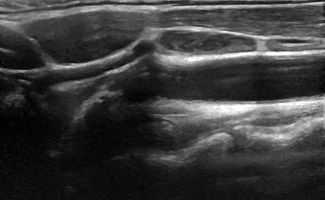

Το Υπερηχογράφημα Λεμφαδένων Τραχήλου προσφέρει μια εμπεριστατωμένη εικόνα των λεμφαδένων, με χρήση της προηγμένης τεχνολογίας των ειδικών κεφαλών υψηλής συχνότητας, Έγχρωμου Doppler, Power Doppler και B-Flow, καθώς και της Ελαστογραφίας. Με αυτές τις τεχνικές είναι δυνατή η γρήγορη και αξιόπιστη αξιολόγηση της μορφολογίας των λεμφαδένων και η αναγνώριση των χαρακτηριστικών τους με μεγάλη ακρίβεια.